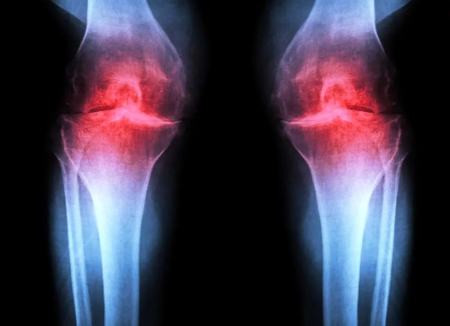

آزمایش موفقیتآمیز داروی جدیدی که میتواند «آرتروز» را درمان کند

آزمایش موفقیتآمیز داروی جدیدی که میتواند «آرتروز» را درمان کند مجموعه: اخبار پزشکی به گزارش فرادید، پژوهشگران دانشکدهی پزشکی استنفورد گزارش میدهند که مهار یک پروتئین وابسته به پیری میتواند غضروفی را که بهشکل طبیعی در زانوی موشهای مسن تحلیل میرود، بازسازی کند. در این مطالعه، درمان تزریقی نهتنها غضروف را دوباره ساخت، بلکه پس از آسیبهای زانو نانند پارگی رباط صلیبی قدامی (ACL) که در ورزشکاران و بزرگسالان فعال شایع است، از بروز آرتروز هم جلوگیری کرد. نسخهی خوراکی همین درمان هماکنون در کارآزماییهای بالینی با هدف درمان ضعف عضلانی مرتبط با افزایش سن در حال آزمایش است. بافت زانوی انسان که در جریان جراحیهای تعویض مفصل جمعآوری شده بود هم به این درمان پاسخ مثبت نشان داد. این نمونهها که هم داربست خارجسلولیِ پشتیبان مفصل (ماتریکس) و هم سلولهای تولیدکنندهی غضروف (کندروسیتها) را شامل میشوند، شروع به تشکیل غضروف جدیدی کردند که عملکرد طبیعی داشت. در مجموع، این یافتهها نشان میدهند که شاید در آینده بتوان غضروف از دسترفته بر اثر پیری یا آرتروز را با تزریق موضعی یا داروی خوراکی بازسازی کرد و بهطور بالقوه نیاز به جراحی تعویض زانو یا لگن را از میان برداشت. هدفگیری ریشهی آرتروز این درمان بهجای تسکین نشانهها، عامل زمینهای آرتروز را هدف میگیرد. این بیماری حادشونده مفصلی حدود یکپنجم بزرگسالان ایالات متحده را درگیر میکند و سالانه حدود ۶۵ میلیارد دلار هزینهی مستقیم مراقبتهای سلامت ایجاد میکند. در حال حاضر هیچ دارویی وجود ندارد که بتواند روند بیماری را متوقف یا معکوس کند و مدیریت درد و تعویض مفصل گزینههای اصلی درمان هستند. این درمان پروتئینی به نام 15-PGDH را هدف میگیرد که با افزایش سن فراوانتر میشود و در ردهی «جروزایمها» (gerozymes) قرار میگیرد. جروزایمها که نخستینبار سال ۲۰۲۳ توسط همین گروه پژوهشی توصیف شدند، نقش محوری در پیری دارند و به افت تدریجی عملکرد بافتها کمک میکنند. در موشها، افزایش سطح 15-PGDH عامل کلیدی کاهش قدرت عضلانی مرتبط با سن است. هنگامی که دانشمندان این پروتئین را با یک مولکول کوچک مهار میکنند، موشهای مسن افزایش تودهی عضلانی و استقامت نشان میدهند. در مقابل، واداشتن موشهای جوان به تولید 15-PGDH سبب ضعف و تحلیل عضلات آنها میشود. این پروتئین همچنین با بازسازی سلولهای استخوانی، عصبی و خونی مرتبط دانسته شده است. در آن بافتها، ترمیم به فعالسازی و تمایز سلولهای بنیادی اختصاصی بافت وابسته است. اما غضروف رفتار متفاوتی دارد. بهجای اتکا به سلولهای بنیادی، کندروسیتها فعالیت ژنی خود را بهگونهای تغییر میدهند که حالت جوانتری را بازمییابد و بازسازی بدون دخالت سلولهای بنیادی رخ میدهد. هلن بلو، دکترای میکروبیولوژی و ایمنیشناسی گفته: «این یک روش جدید برای بازسازی بافت بالغ است و نوید بالینی قابلتوجهی برای درمان آرتروز ناشی از پیری یا آسیب دارد. ما بهدنبال سلولهای بنیادی بودیم، اما بهوضوح دخالتی ندارند. این بسیار هیجانانگیز است.» بوتانی گفته: «میلیونها نفر با افزایش سن از درد و تورم مفاصل رنج میبرند. این یک نیاز درمانی بزرگ و برآوردهنشده است. تا به امروز هیچ دارویی وجود نداشت که مستقیم دلیل از دست رفتن غضروف را درمان کند. اما این مهارکنندهی گروزایم سبب بازسازی چشمگیر غضروف شده؛ فراتر از آنچه در پاسخ به هر دارو یا مداخلهی دیگری گزارش شده.» سه نوع اصلی غضروف در بدن انسان وجود دارد. غضروف الاستیک نرم و انعطافپذیر است و ساختارهایی مانند لالهی گوش را تشکیل میدهد. غضروف فیبری (فیبروغضروف) متراکم و سخت است و ضربه را در نواحی مانند بین مهرههای ستون فقرات جذب میکند. نوع سوم، غضروف هیالین، صاف و براق است و سطحی کماصطکاک برای روانسازی و انعطافپذیری مفاصل مانند مچ پا، لگن، شانه و بخشهایی از زانو فراهم میکند. غضروف هیالین که به آن غضروف مفصلی هم گفته میشود، بیشترین درگیری را در آرتروز دارد. آرتروز زمانی رخ میدهد که مفصل بر اثر پیری، آسیب یا چاقی تحت فشار قرار گیرد. کندروسیتها شروع به آزادسازی مولکولهای پیشالتهابی و تجزیهی کلاژن (پروتئین ساختاری اصلی غضروف) میکنند. با از دست رفتن کلاژن، غضروف نازک و نرم میشود و التهاب همراه، تورم و درد مفصل را (که از ویژگیهای بارز بیماری است) ایجاد میکند. در شرایط عادی، غضروف مفصلی بهندرت بازسازی میشود. اگرچه برخی جمعیتهای فرضی از سلولهای بنیادی یا پیشسازِ قادر به تولید غضروف در استخوان شناسایی شدهاند، تلاشها برای یافتن جمعیتهای مشابه در غضروف مفصلی موفقیتآمیز نبوده است. پژوهشهای پیشین آزمایشگاه بلو نشان داده بود مولکولی به نام پروستاگلاندین E۲ برای عملکرد سلولهای بنیادی عضله ضروری است. 15-PGDH پروستاگلاندین E۲ را تجزیه میکند. مهار فعالیت 15-PGDH یا افزایش سطح پروستاگلاندین E۲ از بازسازی عضله، عصب، استخوان، کولون، کبد و سلولهای خونی آسیبدیده در موشهای جوان پشتیبانی میکند. بلو، بوتانی و همکارانشان بررسی کردند که آیا 15-PGDH در پیری غضروف و مفاصل هم نقش دارد یا خیر و آیا مسیر مشابهی در از دست رفتن غضروف بر اثر پیری یا در پاسخ به آسیب دخیل است. مقایسهی میزان 15-PGDH در غضروف زانوی موشهای جوان و پیر نشان داد که همانند سایر بافتها، سطح این گروزایم با افزایش سن حدود دو برابر میشود. سپس آنها با تزریق یک داروی مولکول کوچکِ مهارکنندهی 15-PGDH به حیوانات پیر (ابتدا به داخل شکم با اثر سیستمیک و سپس مستقیما به مفصل) آزمایش کردند. در هر دو حالت، غضروف زانو که در حیوانات مسن نسبت به موشهای جوان بهطور محسوسی نازکتر و کمکارتر بود، در سراسر سطح مفصل ضخیمتر شد. آزمایشهای تکمیلی تأیید کرد که کندروسیتهای مفصل در حال تولید غضروف هیالین (مفصلی) هستند، نه فیبروغضروفِ کمکارتر. بوتانی درباره این آزمایش گفته: «بازسازی غضروف تا این حد در موشهای مسن ما را شگفتزده کرد. اثر آن چشمگیر بود.» پرداختن به پارگیهای ACL نتایج مشابهی در حیوانات دارای آسیبهای زانو مانند پارگی ACL که در ورزشهایی چون فوتبال، بسکتبال و اسکی با چرخشهای ناگهانی، توقف یا پرش رخ میدهد، مشاهده شد. اگرچه این پارگیها قابلترمیم با جراحی هستند، حدود ۵۰٪ افراد طی حدود ۱۵ سال در مفصل آسیبدیده دچار آرتروز میشوند. پژوهشگران دریافتند مجموعهای از تزریقها، دو بار در هفته به مدت چهار هفته پس از آسیب، از مهارکنندهی گروزایم به شکل چشمگیری احتمال بروز آرتروز در موشها را کاهش میدهد. حیواناتی که داروی کنترل دریافت کرده بودند، سطح 15-PGDH آنها دو برابر همتایان بدون آسیب بود و ظرف چهار هفته به آرتروز مبتلا شدند. حیواناتِ درمانشده با مهارکنندهی گروزایم همچنین الگوی حرکتی طبیعیتری داشتند و وزن بیشتری را روی پنجهی پای آسیبدیده میگذاشتند. بلو گفته: «جالب اینجاست که پروستاگلاندین E۲ با التهاب و درد مرتبط دانسته شده، اما این پژوهش نشان میدهد در سطوح زیستی طبیعی، افزایشهای کوچک پروستاگلاندین E۲ میتواند بازسازی را تقویت کند.» بررسی دقیقتر کندروسیتها در مفاصل موشهای پیر و جوان نشان داد که کندروسیتهای پیر بیان ژنهای مضرِ بیشتری مرتبط با التهاب و تبدیل غضروف هیالین به استخوان ناخواسته دارند و در مقابل، ژنهای کمتری مرتبط با تکوین غضروف بیان میکنند. برنامهریزی مجدد سلولهای غضروف بدون سلولهای بنیادی پژوهشگران همچنین توانستند زیرگروههایی از کندروسیتهای پیر را شناسایی کنند که پس از درمان الگوی بیان ژن آنها تغییر میکند. یکی از این زیرگروهها که 15-PGDH و ژنهای دخیل در تخریب غضروف را بیان میکند، پس از درمان از ۸٪ به ۳٪ کاهش یافت. زیرگروه دیگری که 15-PGDH را بیان نمیکند اما ژنهای تولید فیبروغضروف را بیان میکند هم از ۱۶٪ به ۸٪ کاهش یافت. در مقابل، جمعیت سومی که 15-PGDH تولید نمیکند و ژنهای دخیل در تشکیل غضروف هیالین و حفظ ماتریکس خارجسلولیِ لازم برای عملکرد آن را بیان میکند، پس از درمان از ۲۲٪ به ۴۲٪ افزایش یافت. این یافتهها گواه یک جابهجایی کلی در بیان ژنها به سوی ترکیب غضروفی جوانتر است، بدون دخالت سلولهای بنیادی یا پیشساز. در نهایت، پژوهشگران بافت غضروف انسانیِ برداشتهشده از بیماران مبتلا به آرتروز که تحت تعویض کامل زانو قرار داشتند را بررسی کردند. بافتی که مدت یک هفته با مهارکنندهی 15-PGDH تیمار شده بود، نسبت به بافت کنترل، سطوح پایینتری از کندروسیتهای بیانکنندهی 15-PGDH و کاهش ژنهای تخریب غضروف و فیبروغضروف نشان داد و شروع به بازسازی غضروف مفصلی کرد. بوتانی گفته: «این سازوکار بسیار چشمگیر است و به راستی دیدگاه ما را دربارهی چگونگی وقوع بازسازی بافت تغییر داد. روشن است که مخزن بزرگی از سلولهای ازپیشموجود در غضروف در حال تغییر الگوهای بیان ژنی خود هستند. با هدفگیری این سلولها برای بازسازی، ممکن است از دید بالینی اثر کلی بزرگتری ایجاد کنیم.» بلو افزود: «کارآزماییهای بالینی فاز ۱ مهارکنندهی 15-PGDH برای ضعف عضلانی نشان دادهاند که این دارو در داوطلبان سالم ایمن و فعال است. امید ما اینست که بهزودی کارآزمایی مشابهی برای سنجش اثر آن در بازسازی غضروف آغاز شود. ما از این دستاورد بالقوه بسیار هیجانزدهایم. تصور کنید غضروف موجود دوباره رشد کند و از تعویض مفصل اجتناب شود.»